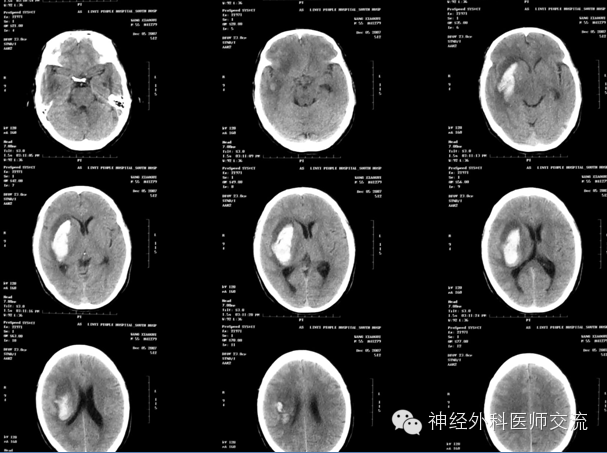

很普通的病例,术后4小时,突发脑疝,静推1瓶甘露醇,急查CT

从三通侧臂,抽不出血来。拔除引流导管,按照新的CT,从原骨孔重新置管,从新操作

远端的血清掉后,回撤导管,再液化引流

原因:术后病人烦躁、血压恶性升高,致再出血,导成血肿扩大。

不正规的操作易出并发症-出血